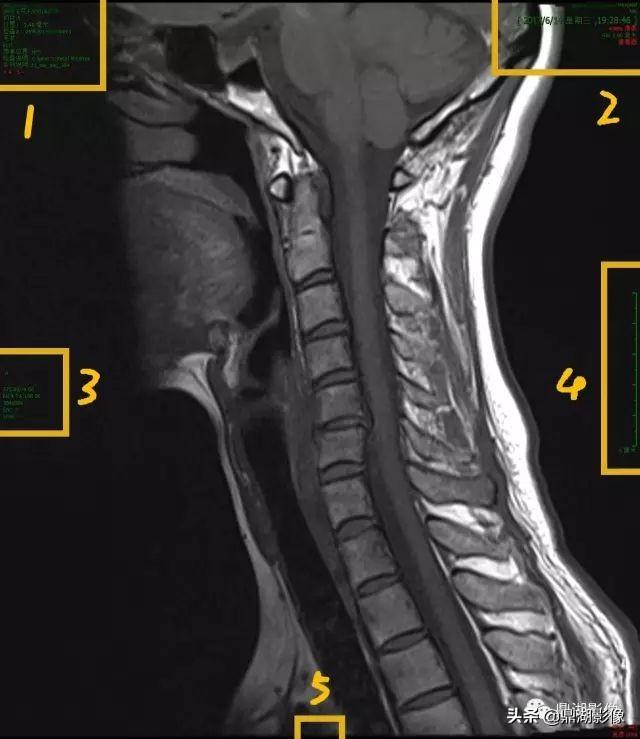

MRI

这是一张影像片子中的一个层面/一张图像,图像一般分为几个区,右上为患者及检查信息,左上为机器及图片信息,左下为扫描条件,右下为显示视野。如果需要分辨左右的关节,比如膝关节、踝关节等等,都会通过L(左)或R(右)来标注。

放大1区:

1.患者姓名,一般为汉语拼音,有的是汉字标示;

2.患者年龄、性别及影像检查号,其中M为男性,F为女性;

3.影像登记流水号,告诉患者登记的顺序,如图中说明这个患者是2017年6月13号第13个登记的;

4.图像编号,图中这是序列中第5副图;

5.检查部位C_Spine为颈椎

6.序列:矢状位T1,TSE

放大2区:

1.所做检查医院名称,一般带有XX Hosptial或XX医院;

2.检查日期,顺序为年月日;

3.检查时间,精确到秒;

4.SW为层厚,图中检查层厚为3.00mm